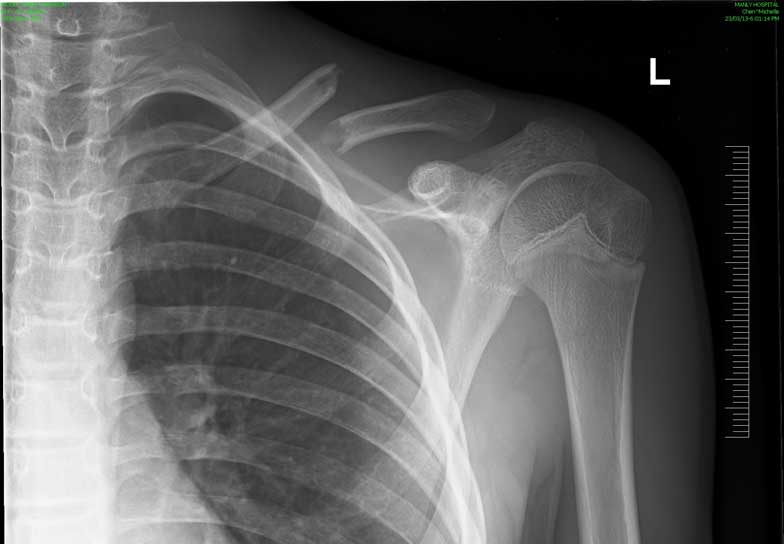

What do clavicle fractures look like on X-ray?

Below are examples of typical fractures that benefit from surgery.

Click an image to enlarge

A 15 year old female fell from her pushbike causing a displaced left mid-shaft clavicular fracture. Seen 5 days later, plate & screws inserted 2 days later.

Image

DIsplaced fracture before surgery

DIsplaced fracture after surgery

Move the slider to compare before surgery and after surgery